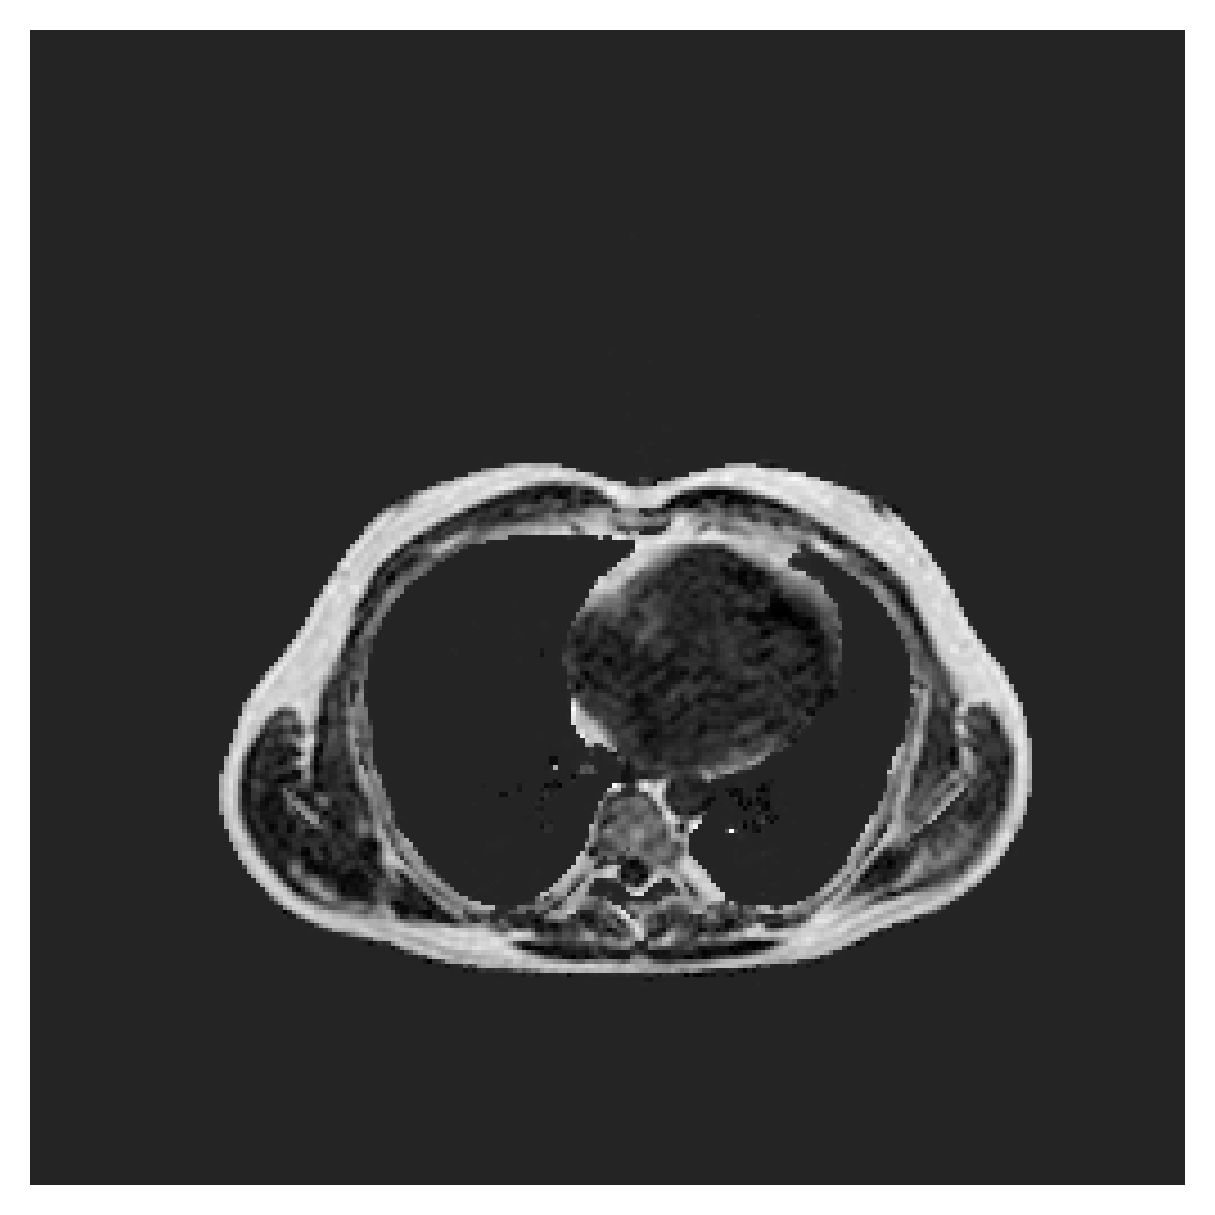

5.1 Segmentation of cardiac structures

The average 3D Dice scores and HD95 values on the ACDC test set are given in Table 2, and boxplots in figures 4 and 5 show the distributions. We see that, in terms of DSC, the proposed strategy of using intensity-aware distances withing boundary loss performs better than simply using the Euclidean distance, with the best results achieved by using the strictly intensity based MBD. The HD95 however favors the original version of , which may be do to its smoother predictions and less fragmentation and oversegmentation. The CRF-loss results are significantly worse in both metrics.

In Figure 6 we provide qualitative results on a number of randomly chosen test set slices. Upon visual inspection, we can observe that training with the intensity-aware distances (particularly with and ) follows the image gradients better and is better at recovering the underlying shape than the Euclidean version. The CRF-loss seems to recover the shape of the myocardium and left ventricle to some extent, but fails entirely on the right ventricle.